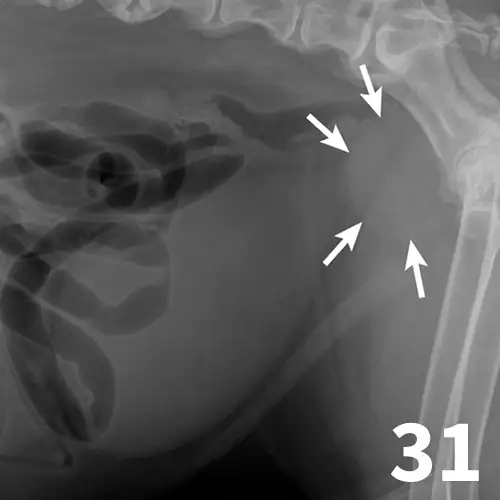

Survey radiography can be used to evaluate the size, shape, and opacity of the prostate gland (Figures 31 and 32). Ultrasonography has the advantage of providing tissue-architecture information. Prostatic abscesses, internal cysts, and paraprostatic cysts are readily visualized on ultrasonography. Ultrasonography can also aid in diagnosing benign hyperplasia (homogenous echotexture with intact capsule) and prostatic neoplasia (heterogenous with course echotexture and irregular margins) (Figure 33) and with identifying any potential source of excess androgen production (eg, adrenal glands, retained testes) in cases of suspected squamous metaplasia of the prostate gland. Mineralization of the prostate in a neutered dog is suggestive of neoplasia and can be detected by both survey radiography and ultrasonography. Sublumbar lymph nodes can also be evaluated by ultrasonography, whereas radiography is best for evaluating the adjacent lumbar spine (Figures 34 and 35).

Figure 31.

The prostate gland (arrows) in this intact male dog is enlarged but normal in shape with smooth margins and soft tissue opacity. Although this is consistent with benign prostatic hypertrophy, ultrasound would be useful to further define tissue architecture.